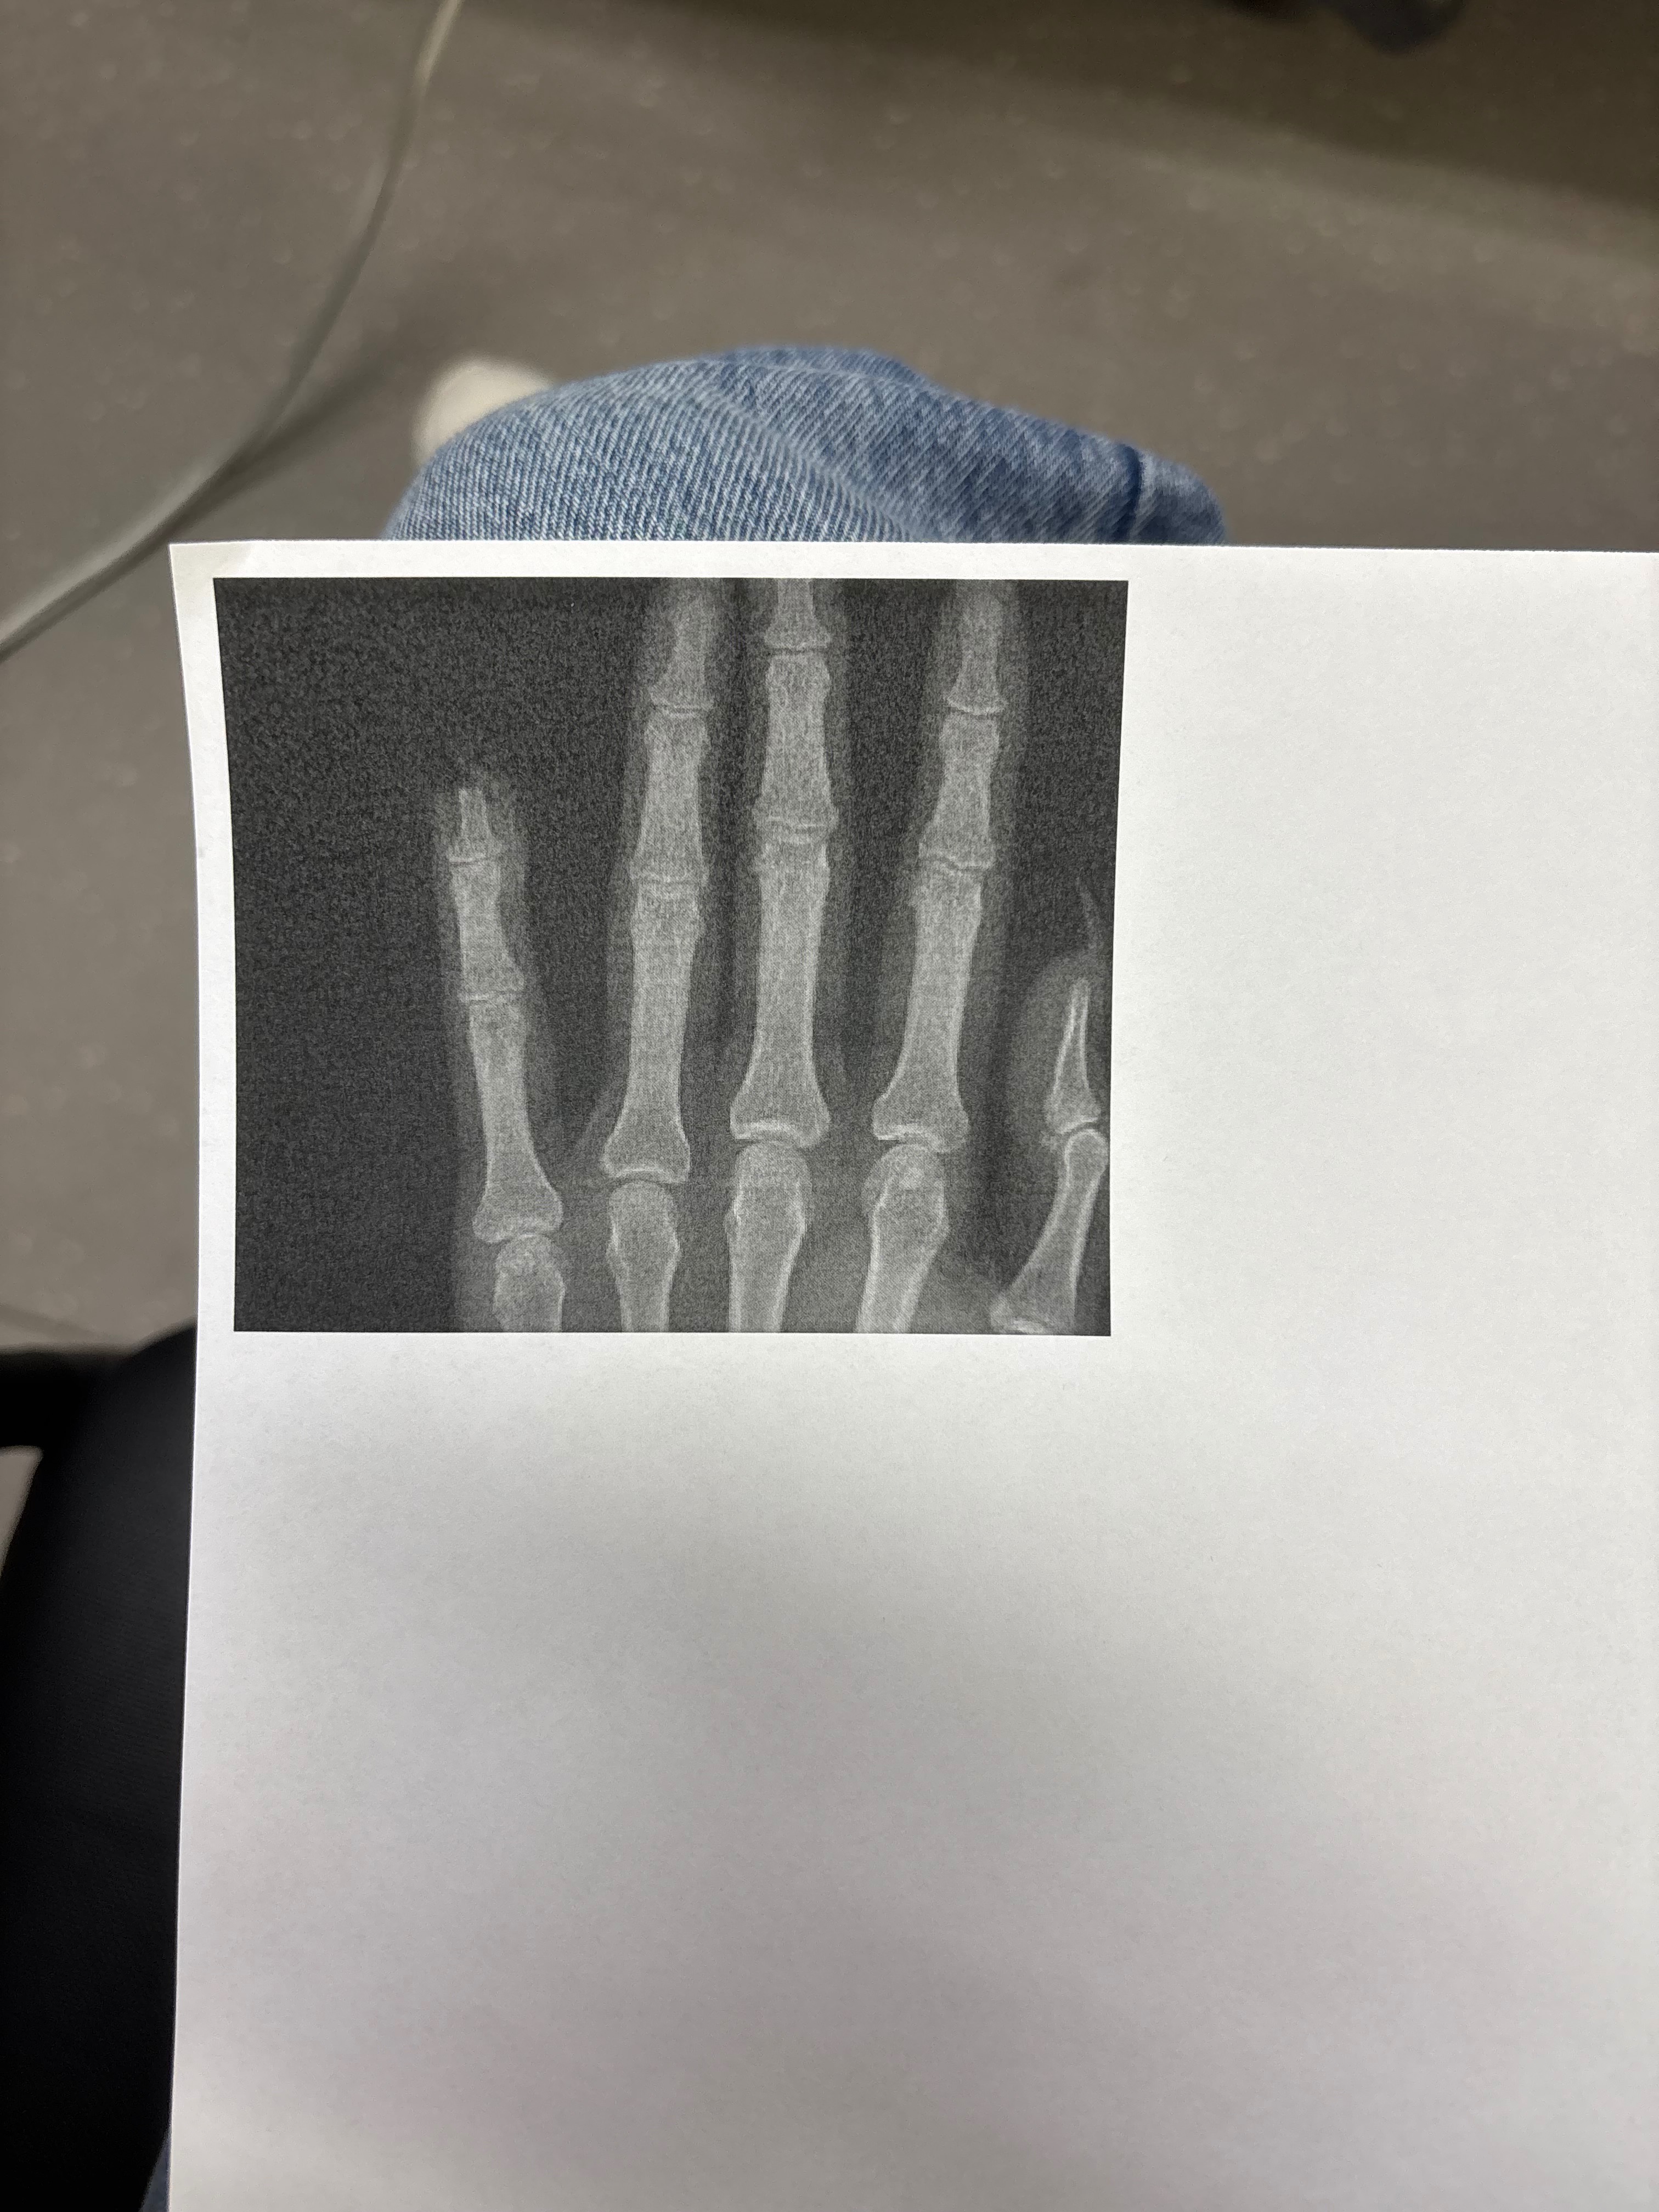

On Friday, December 5th, my friend Jaycee experienced a traumatic accident when her finger was caught in a bike chain. In the struggle to free herself, her pinky finger was severed at the first knuckle, leaving bone exposed and the entire top of her finger missing. She rushed to the ER with her fingertip on ice, but was sent home with only gauze and no real treatment. Desperate for help, Jaycee tried another hospital, but they did not have a hand specialist available and referred her to a surgeon for an outpatient procedure.